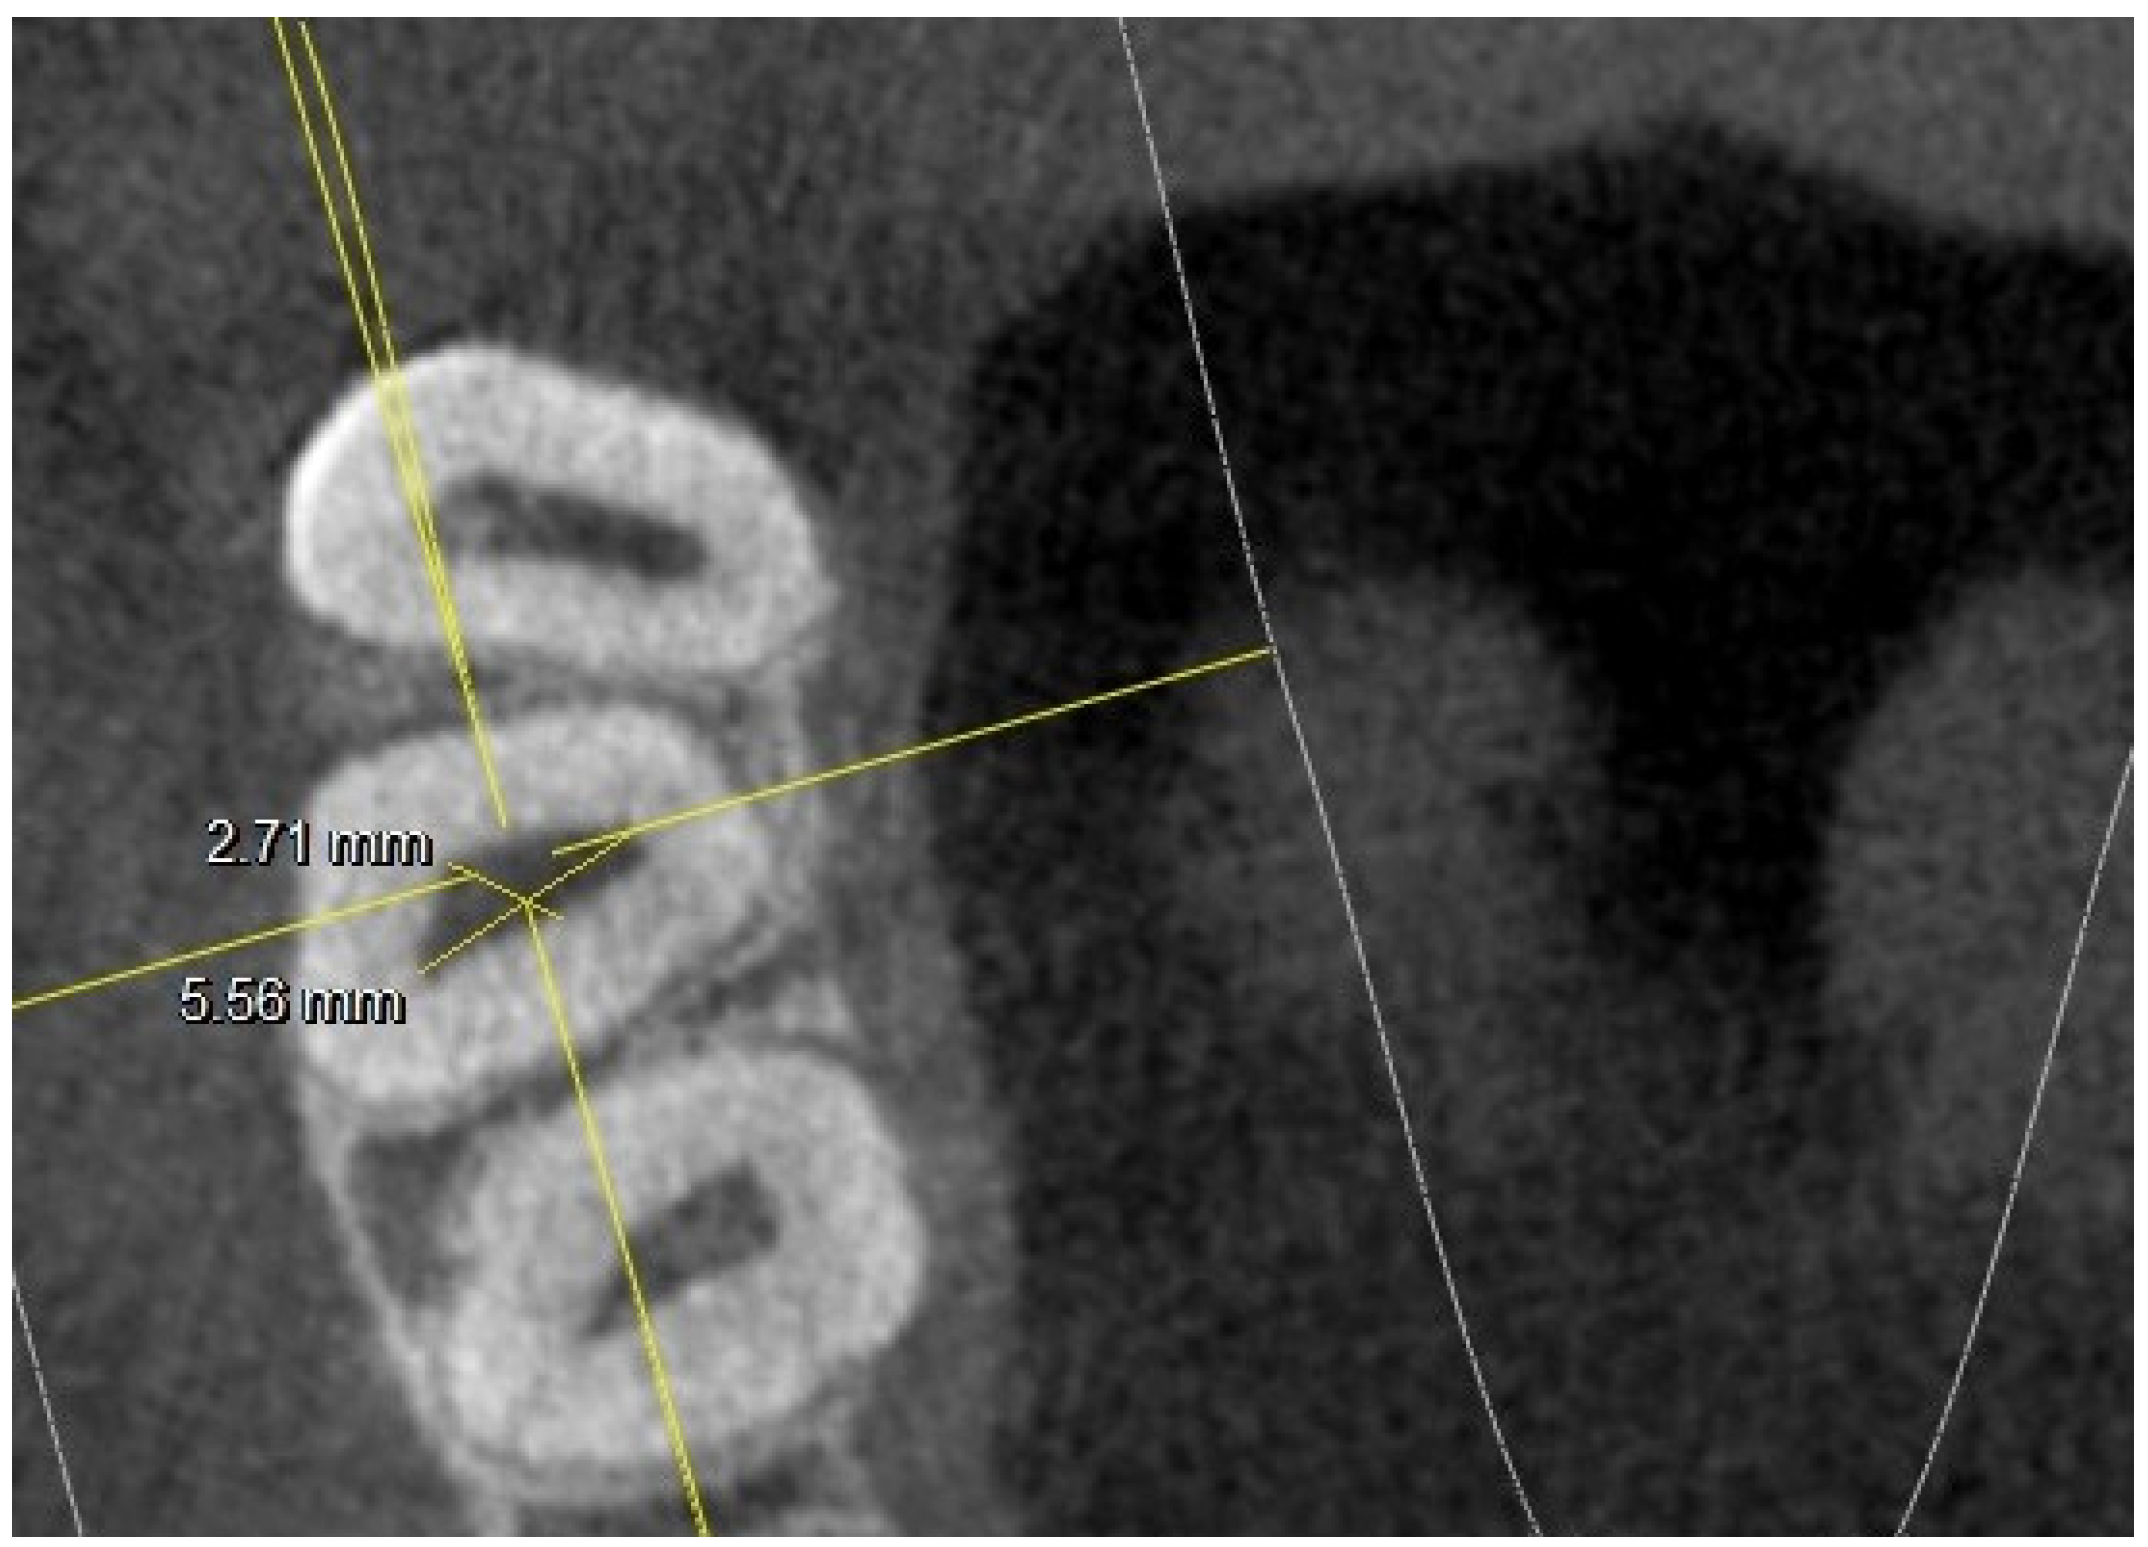

- long and short diameter of the pulp chamber floor;

- diameter of root canal orifices;

- distance between intra- and inter-root canals;

| At the orifice: MB-DB distance | 2.33 | 0.22 | 2.35 | 0.21 | 2.22 | 0.2 | 2.19 | 0.2 | ||

| MB1-MB2 distance | 1.54 | 0.21 | 1.67 | 0.21 | 1.63 | 0.19 | 1.45 | 0.22 | ||

| MB-P distance | 4.91 | 0.3 | 5.03 | 0.36 | 5.02 | 0.26 | 4.87 | 0.31 | ||